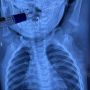

Врачи напоминают, что с наступлением похолоданий самое эффективное средство защиты от вирусов — вакцинация.

Прививка помогает организму заранее подготовиться к встрече с инфекцией и снижает риск тяжёлого течения болезни.